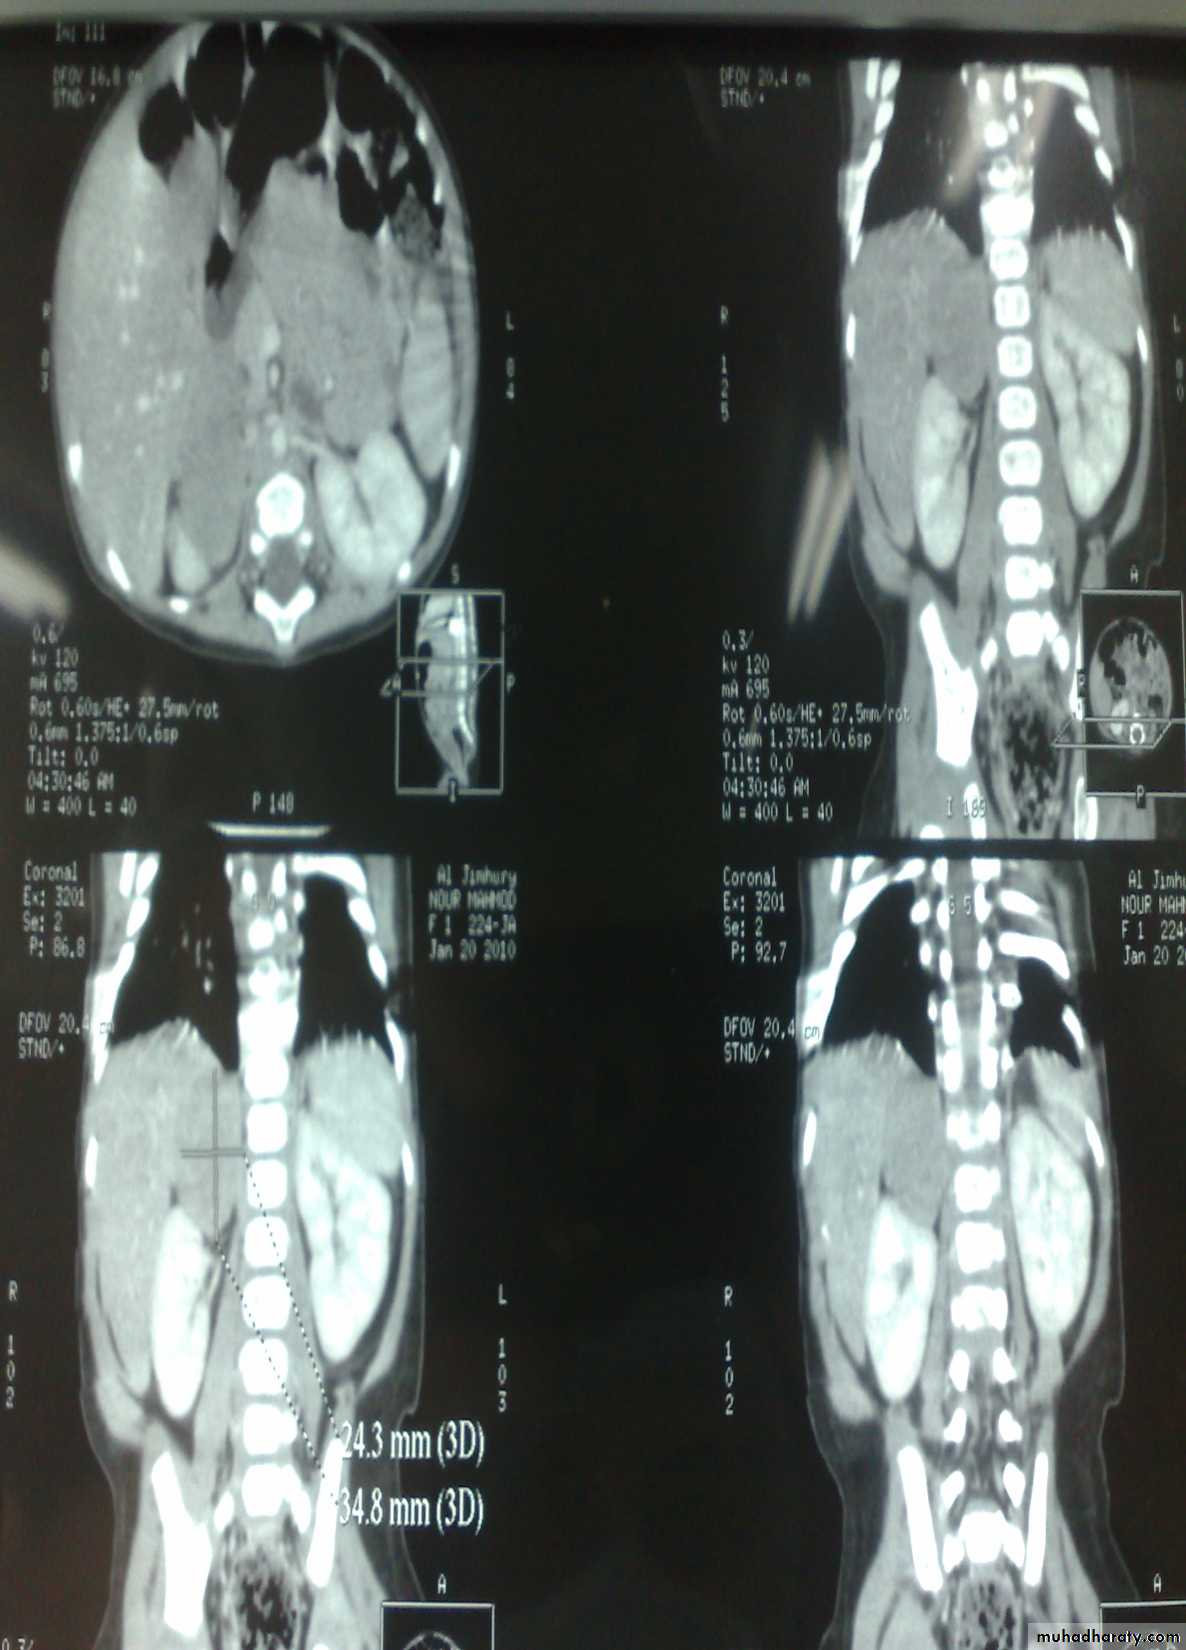

The Child with an Abdominal Mass